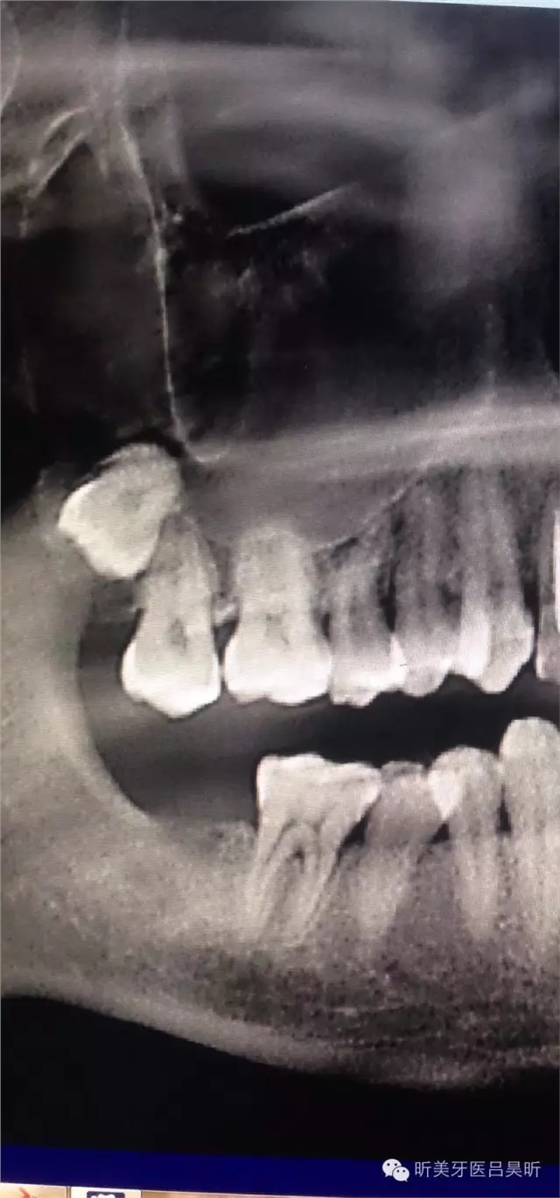

術(shù)前CBCT截圖,垂直骨量似乎感覺良好

可見種植位點(diǎn)舌側(cè)區(qū)凹陷,牙槽骨上部舌傾明顯。